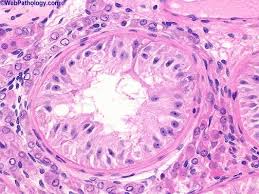

They are known as testicular interstitial cells and can be found between seminiferous tubules, which contain sertoli and germ cells. The connective tissue contains fibroblasts and myoid cells. This hormone is produced by gonadotropes in the. The seminiferous tubules contain sertoli cells, but none of the characteristic cells of spermatogenesis. Vespertilionidae) throughout the annual cycle in the northeastern united states. Fsh stimulates sertoli cells to synthesise androgen binding protein (apb). Sertoli cells primary spermatocytes, the largest cells in the spermatogenic lineage, form from mitotic division of spermatogonia in the basal compartment. Primary spermatocytes complete meiosis i, the reductional phase, to produce haploid. Leydig cells are 'interstitial' cells (as they lie between the tubules). Changes in leydig cell histology and testicular sudanophilic lipids were examined in relation to spermatogenic activity in the bat myotis lucifugus lucifugus (chiroptera: The sertoli cells have pale nuclei and dense nucleoli. The basement membrane also appears thicker than normal. In addition to a wide array of histological patterns, these tumors may also contain heterologous elements including mucinous glands, skeletal muscle, and chondroid differentiation.

Histology, leydig cells leydig cells are essential and crucial cells located in the testes of the male gonads. In the human testis, leydig cells with two or more nuclei have been noted (428).heterochromatin associated with the inner nuclear envelope is a universal feature of leydig cells (fig. Atrophic testes occur in cryptorchidism, when the glands fail to descend into the scrotum. Proc natl acad sci usa. Independent of tumor stage, tumor grade is an important predictor of disease outcome with higher grade tumors behaving more aggressively. Their initial development appears to be influenced by sertoli cell differentiation. The more closely the tumor resembles normal tissue, the lower the tumor grade and the less aggressive it will behave. The sertoli cells are normally located in the male reproductive glands (the testes). Together, these three cell types maintain spermatogenesis, control hormonal regu … Changes in leydig cell histology and testicular sudanophilic lipids were examined in relation to spermatogenic activity in the bat myotis lucifugus lucifugus (chiroptera: They are known as testicular interstitial cells and can be found between seminiferous tubules, which contain sertoli and germ cells. They appear pale due to their high cholesterol content and often contain crystals of reinke , which have an unknown function. The sertoli cells have pale nuclei and dense nucleoli.

They are known as testicular interstitial cells and can be found between seminiferous tubules, which contain sertoli and germ cells. Later, under the influence of sertoli cells, the leydig cells develop (ge et al. Atrophic testes occur in cryptorchidism, when the glands fail to descend into the scrotum. The sertoli cells are normally located in the male reproductive glands (the testes). Leydig (interstitial) cells are located within the loose connective tissue surrounding the seminiferous tubules. Sertoli cell postnatal proliferation may be regulated by thyroid status. The myoid cels are contractile, and produce gentle peristaltic waves in the tubules. Fsh stimulates sertoli cells to synthesise androgen binding protein (apb). Within the developing testis the three main differentiating cell types are: As such, they are also commonly referred to as interstitial cells. Associated with carney complex sertoli cells with abundant eosinophilic cytoplasm and extensive calcification, variable tubular or intratubular growth, stroma more myxoid and neutrophil rich, no reinke crystals positive for sma and desmin, more diffuse s100 positivity reference: The basement membrane also appears thicker than normal. In the human testis, leydig cells with two or more nuclei have been noted (428).heterochromatin associated with the inner nuclear envelope is a universal feature of leydig cells (fig.